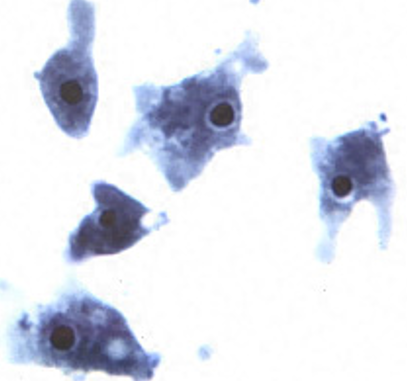

whats this

Trophozoites of Trichomonas vaginalis